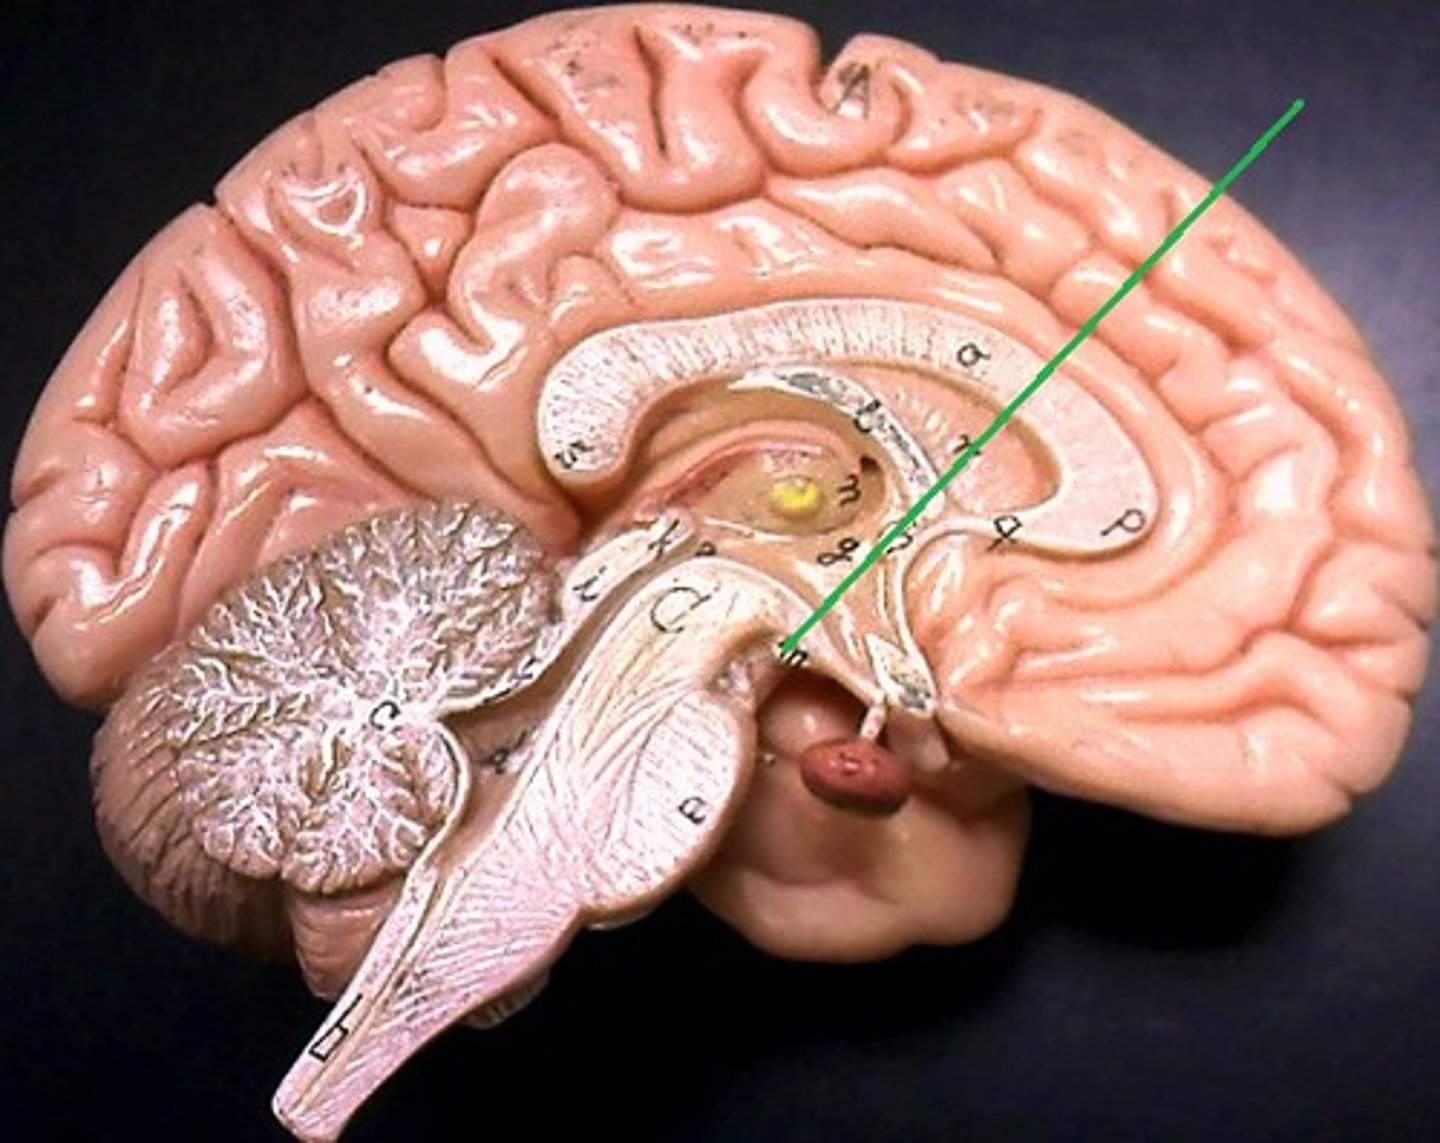

lateral ventricles

third ventricle

fourth ventricle

interventricular foramen

connects lateral ventricles to third ventricle

cerebral aqueduct

connects the third and fourth ventricles

choroid plexus

on the floor of all the ventricles, produces CSF

arachnoid villi

diencephalon

thalamus and hypothalamus

thalamus

relay station for all somatosensory information

intermediate mass

connection between the two thalami across the third ventricle, dumbbell shape

hypothalamus

brain region (many nuclei) in charge of maintaining homeostasis

pituitary gland

produces hormones

mammillary bodies

olfactory relay stations

epithalamus

region above midbrain that contains pineal gland

pineal gland

regulates sleep-wake cycles, secretes melatonin

cerebellum

balance, equilibrium, gross motor movement

corpus callosum

the large band of neural fibers connecting the two brain hemispheres and carrying messages between them

septum pellucidum

membrane that separates lateral ventricles

basal nuclei

internal masses of gray matter, smooth out motor movement

fornix

band under septum pellucidum